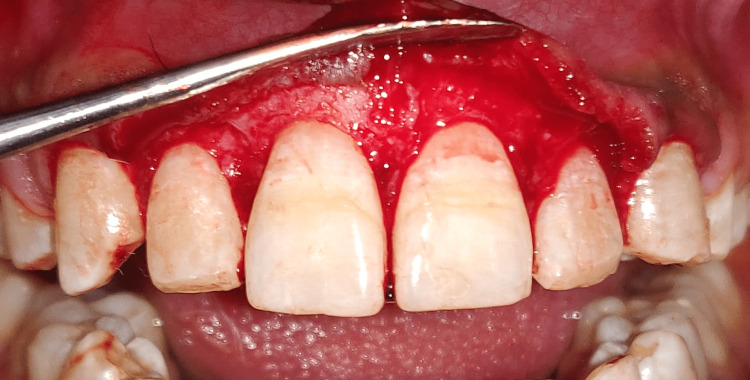

Prophylaxis, oral hygiene teaching, and crown lengthening procedure (CLP) were all part of the treatment regimen. On the first visit, oral prophylaxis was done, followed by instructions on oral hygiene, and the patient was summoned back six weeks later for another evaluation and surgical treatment. Teeth 11-13 and 21-23 underwent aesthetic CLP. After administering a local anesthetic (2% Lidocaine, 1:100,000 epinephrine), bone sounding was carried out to confirm the site of the bony crest. A pocket marker was utilized to create bleeding spots, as shown in Figure 9. Then, a 15 C blade was used to make a scalloped submarginal internal bevel incision on the buccal side only, beginning from the mesial aspect of the right first premolar to the mesial aspect of the left first premolar, as shown in Figure 10. A full thickness mucoperiosteal flap was then reflected using a periosteal elevator after the gingival collar was produced, as shown in Figure 11.

Figure 9. Internal bevel incision in place.

Figure 10. Full thickness mucoperiosteal flap raised.

Figure 11. Placement of sutures after osseous reduction.

To achieve the optimal maxillary anterior crown contours, osseous excision was used to move the bony crest 1-2 mm apical to the CEJ. The flap was sutured back together with non-resorbable sutures (Ethicon Vicryl Sutures USP 3-0, 1/2 Circle Cutting), and a periodontal pack (COE-PAKTM AUTOMIX) was applied to the surgical site. Figure 12 shows sutures and periodontal pack in place. Amoxicillin 500 mg TDS for five days, aceclofenac BD for three days, and 0.12% chlorhexidine rinse twice daily for two weeks were given to the postoperative patient recommendations included using an ice pack, eating soft foods, avoiding mechanical damage to the treated area, and moving your lips as little as possible. After two weeks, the stitches were removed. After surgery, the patient underwent careful follow-up for oral hygiene. Three months following surgery, the patient was reevaluated. Figure 13 shows the postoperative view after three months.